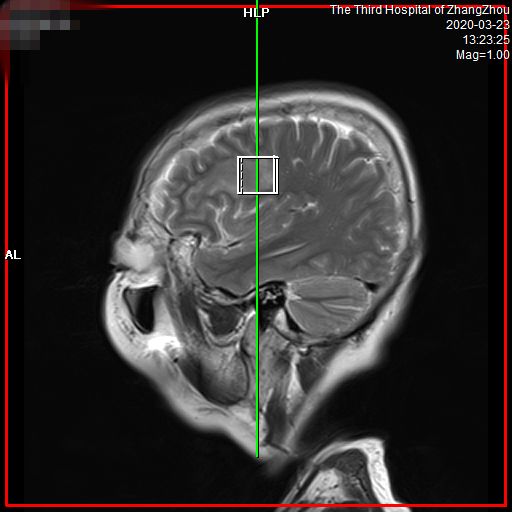

波普分析(MRS)

• 信噪比高,能更早发现小病灶。有关数据显示,对于各类疾病,特别是神经系统和体部系统疾病,可以提前发现病灶,给患者治疗带来了充分的时间,大大提高了病变的诊断水平,让疾病无处可逃,为广大患者带来福音。

脑白质纤维束成像(DTI)